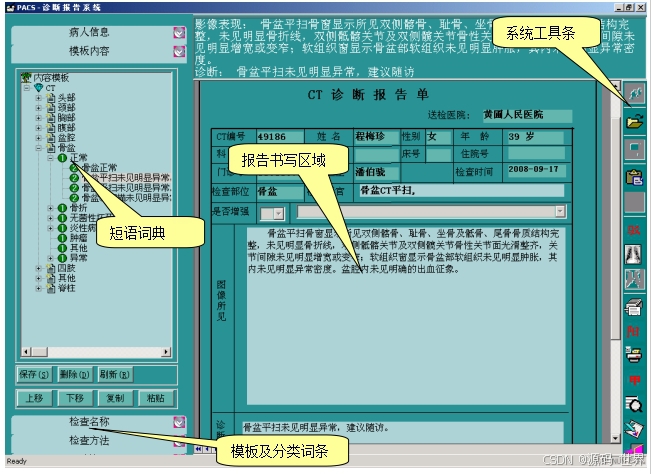

11、影像诊断医生在PACS诊断工作站上书写检查报告。

5、影像工作站:用于医生和专业技术人员查看、诊断、分析及操作影像的计算机和软件系统。